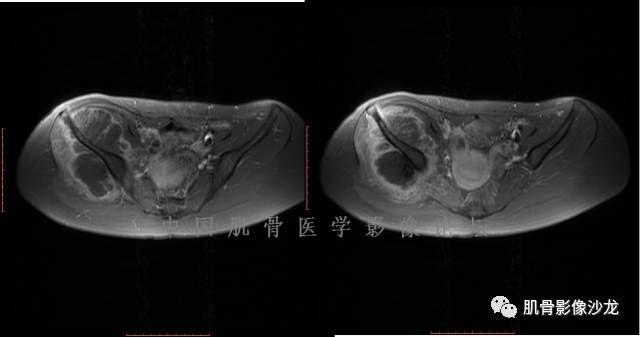

患者2月前无明显诱因下感右腿疼痛、麻木,疼痛呈持续性,发作时无法行走,休息后可缓解。当时无明显肿块,患者遂至当地医院就诊,查X片见右髂骨骨质破坏。6周前患者自觉右髋部渐大肿块,初肿块较小,后肿块逐渐增大,现肿块约12*10cm大小,有压痛。患者遂至我院就诊,查MRI:右髂骨异常信号,伴软组织肿块。ECT、肺CT未见转移。现患者为求进一步治疗,门诊拟“右髂骨肿块 ”收治入院。 患者发病来,神清,精神可,胃纳夜眠可,二便无殊,体重无明显变化。

飞鹰行动 : 第一列可以看见T2小结节样高信号,周围有纤维组织环绕

高回青 : 另外还可以见到扇贝状分叶

1、软骨肉瘤可以有膨胀性骨质破坏(病例3,4),可以有溶骨性骨质破坏(病例2),局部皮质因为破坏变薄,中断 ;

2、软骨基质T2WI高信号,软骨小叶分叶状,也就会出现高老师提到的骨内膜扇贝形压迹。一般认为骨内膜扇贝形压迹超过骨皮质厚度的2/3是软骨肉瘤在长管状骨的特征性表现。如上图。3、软组织肿块或肿胀;